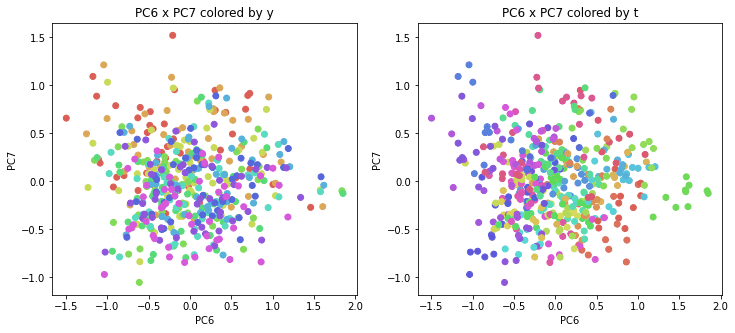

PCAの結果の第n主成分をPCnと表記します。

医療費データの場合と同様に、PCAの結果を見やすく表示するため、seabornのカラーパレットを使って、年月別、都道府県別に色分けして図示してみます(左側が年月別に色分け、右側が都道府県別に色分け)。PC1~PC8まで表示しました。

医療費データの場合ほどはっきりとはしていませんが、PC2が概ね時間の経過を表す成分で、残りの成分が時点によって変わらない地域の特徴を表す成分となっているようです。

また、PC1×PC3を見ると、47沖縄が他の都道府県からかなり離れたところに位置しており、沖縄の地域差が際立っているのが分かります。これは、以前別の記事で年齢階級のない健診データでPCAを実行した場合と似た結果となっています。